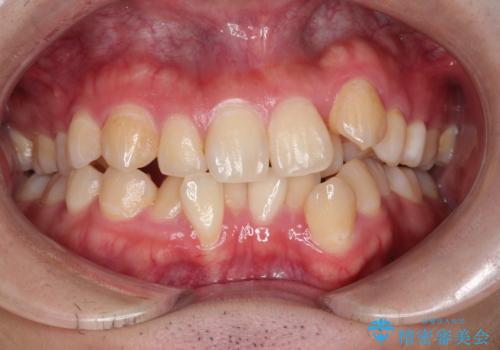

【重度叢生ワイヤー矯正】きれいな歯並びにしたい

- きれいな歯並びにしたいとの希望を持って来院された患者様です。

上下左右小臼歯を抜歯する治療計画を立て審美装置にて治療を行いました。

骨格的3級傾向もあり、咬合関係を仕上げるのに時間がかかりましたが、患者様には大変満足していただけました。